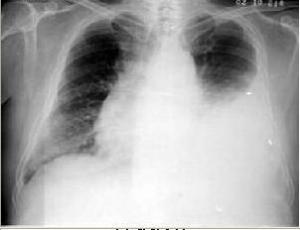

胸腔积液(pleural effusison)是指胸膜腔液体产生与吸收的平衡失调,产生量超过吸收量使胸腔内液体超过正常。老年胸腔积液与中青年有一个很大的不同,前者以癌性胸水为多见,并有逐年增高的趋势,而后者则绝大多数为结核性的。 胸膜炎是致病因素(通常为病毒或细菌)刺激胸膜所致的胸膜炎症。胸腔内可有液体积聚(渗出性胸膜炎)或无液体积聚(干性胸膜炎)。炎症消退后,胸膜可恢复至正常,或发生两层胸膜相互粘连。由多种病因引起,如感染、恶性肿瘤、结缔组织病、肺栓塞等。